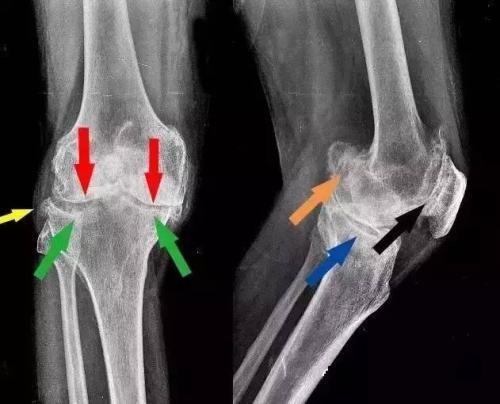

右膝关节内侧平台前缘骨质增生骨赘形成

一文说清骨刺,骨质增生那些事

4种特殊类型的骨刺_关於骨质增生